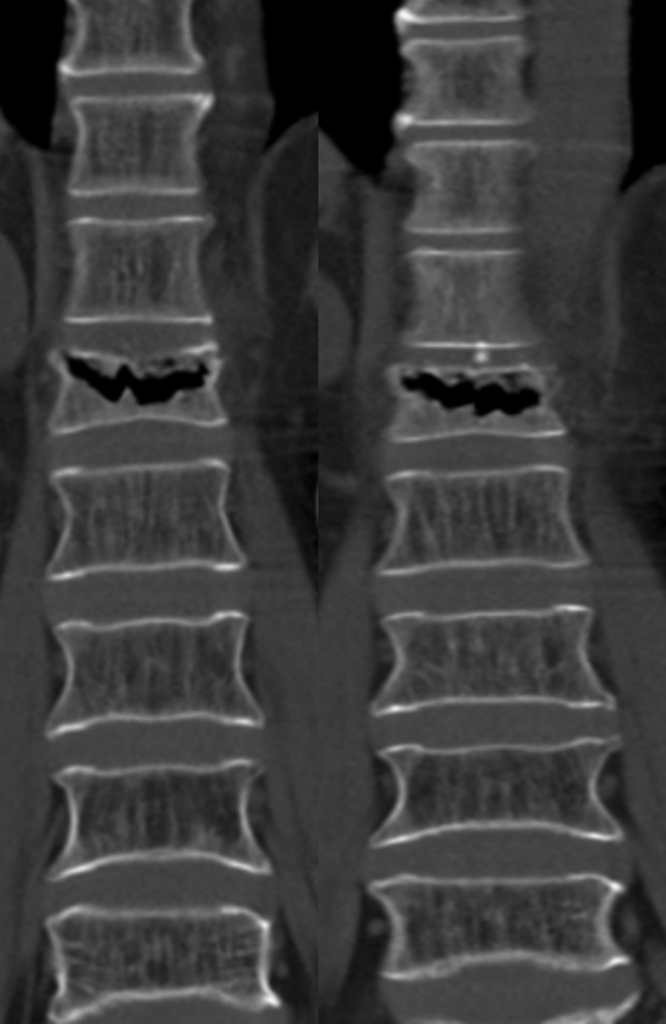

Спондилография: что это такое и зачем она нужна